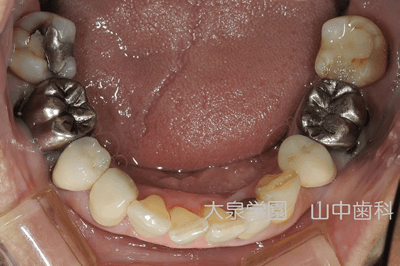

咀嚼時に最も機能する第一大臼歯は審美性と機能性を兼ね備えたメタルセラミックスクラウンを装着し、咬合力が最も大きく伝わる第二大臼歯には機能性を重視したゴールドインレーを装着しました。

審美性を重視し前歯部にオールセラミックスクラウンを装着しました。